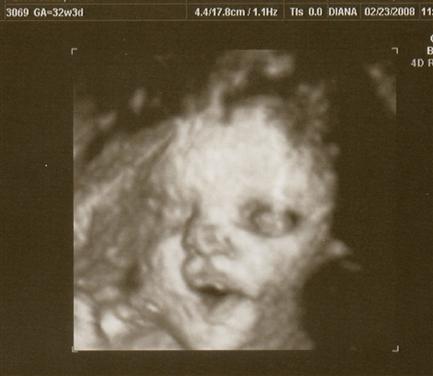

I had my 32 week growth sono on Saturday. Everything is looking good!

is roughly 4.5 - 4.75 pounds and measuring about 1-2 weeks ahead of my scheduled due date. She's in position and all looks good!

The tech took some 3D pics too!! Image Attachment(s):

Aaaaaaaaawww!! Love the one with the parted lips! Blowing kisses to you!!!

Look at those lips!! I can't wait to meet her.